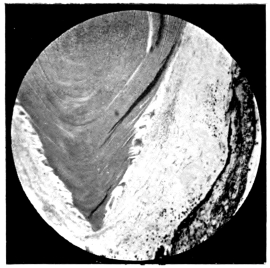

PLATE VI.

34.

L’IRIS BOMBÉ AND RETINAL CYST

curly bracket span

35.

MATTING OF STRUCTURES OF THE EYE DUE TO INFLAMMATION

36.

"       "       "    "     "

(HIGHER MAGNIFICATION)

37.

UNUSUAL APPEARANCE OF EXUDATE INTO THE VITREOUS CAVITY

38.

INFLAMED OPTIC NERVE HEAD

39.

ADVANCED ORGANIZATION OF VITREOUS EXUDATE